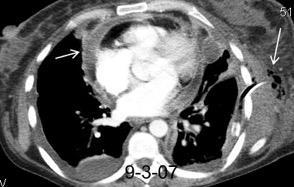

Masa axilar izquierda y derrame pleural derecho. Implantes pleurales, paraespinales . Ganglios en mamaria interna. Linfoma B difuso

Linfoma NH de cél. B. Invasión Transtorácica.

Afectación axilar